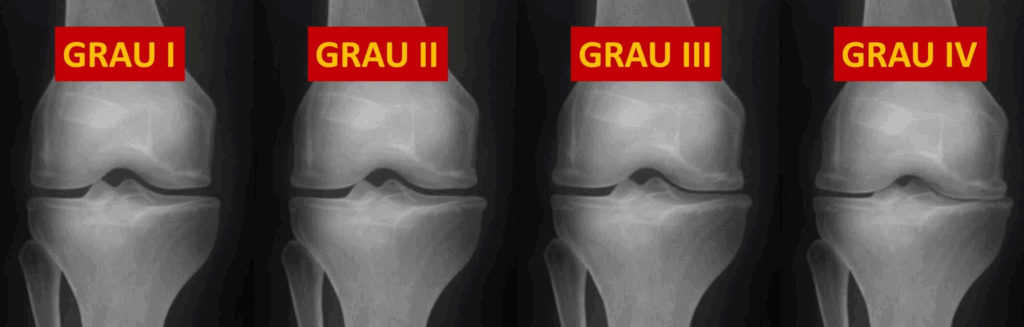

Um dos maiores erros no tratamento da dor no joelho é assumir que toda dor articular é artrose. O simples achado de “desgaste” em um exame de imagem não significa necessariamente que a dor do paciente vem da artrose.

Muitos pacientes apresentam:

- Alterações leves no raio-X sem dor

- Dor intensa com artrose mínima

- Outras causas de dor coexistindo com artrose